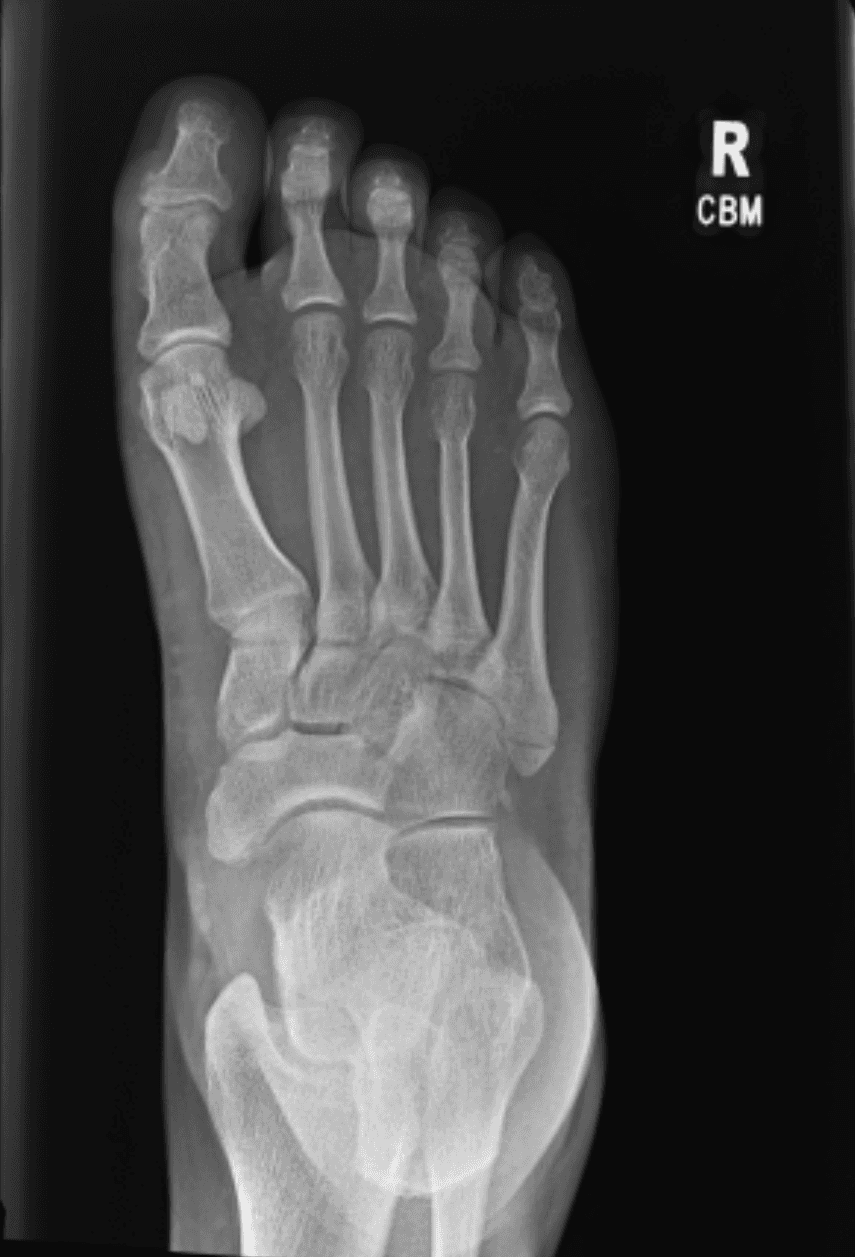

Went to the ER this morning to have my foot looked at. It's definitely broken. They put me in a splint and said not to drive until I see an orthopedist. I told them we were about to drive from Denver to Dayton and they said, "well don't do that". Sorry, Rainey.